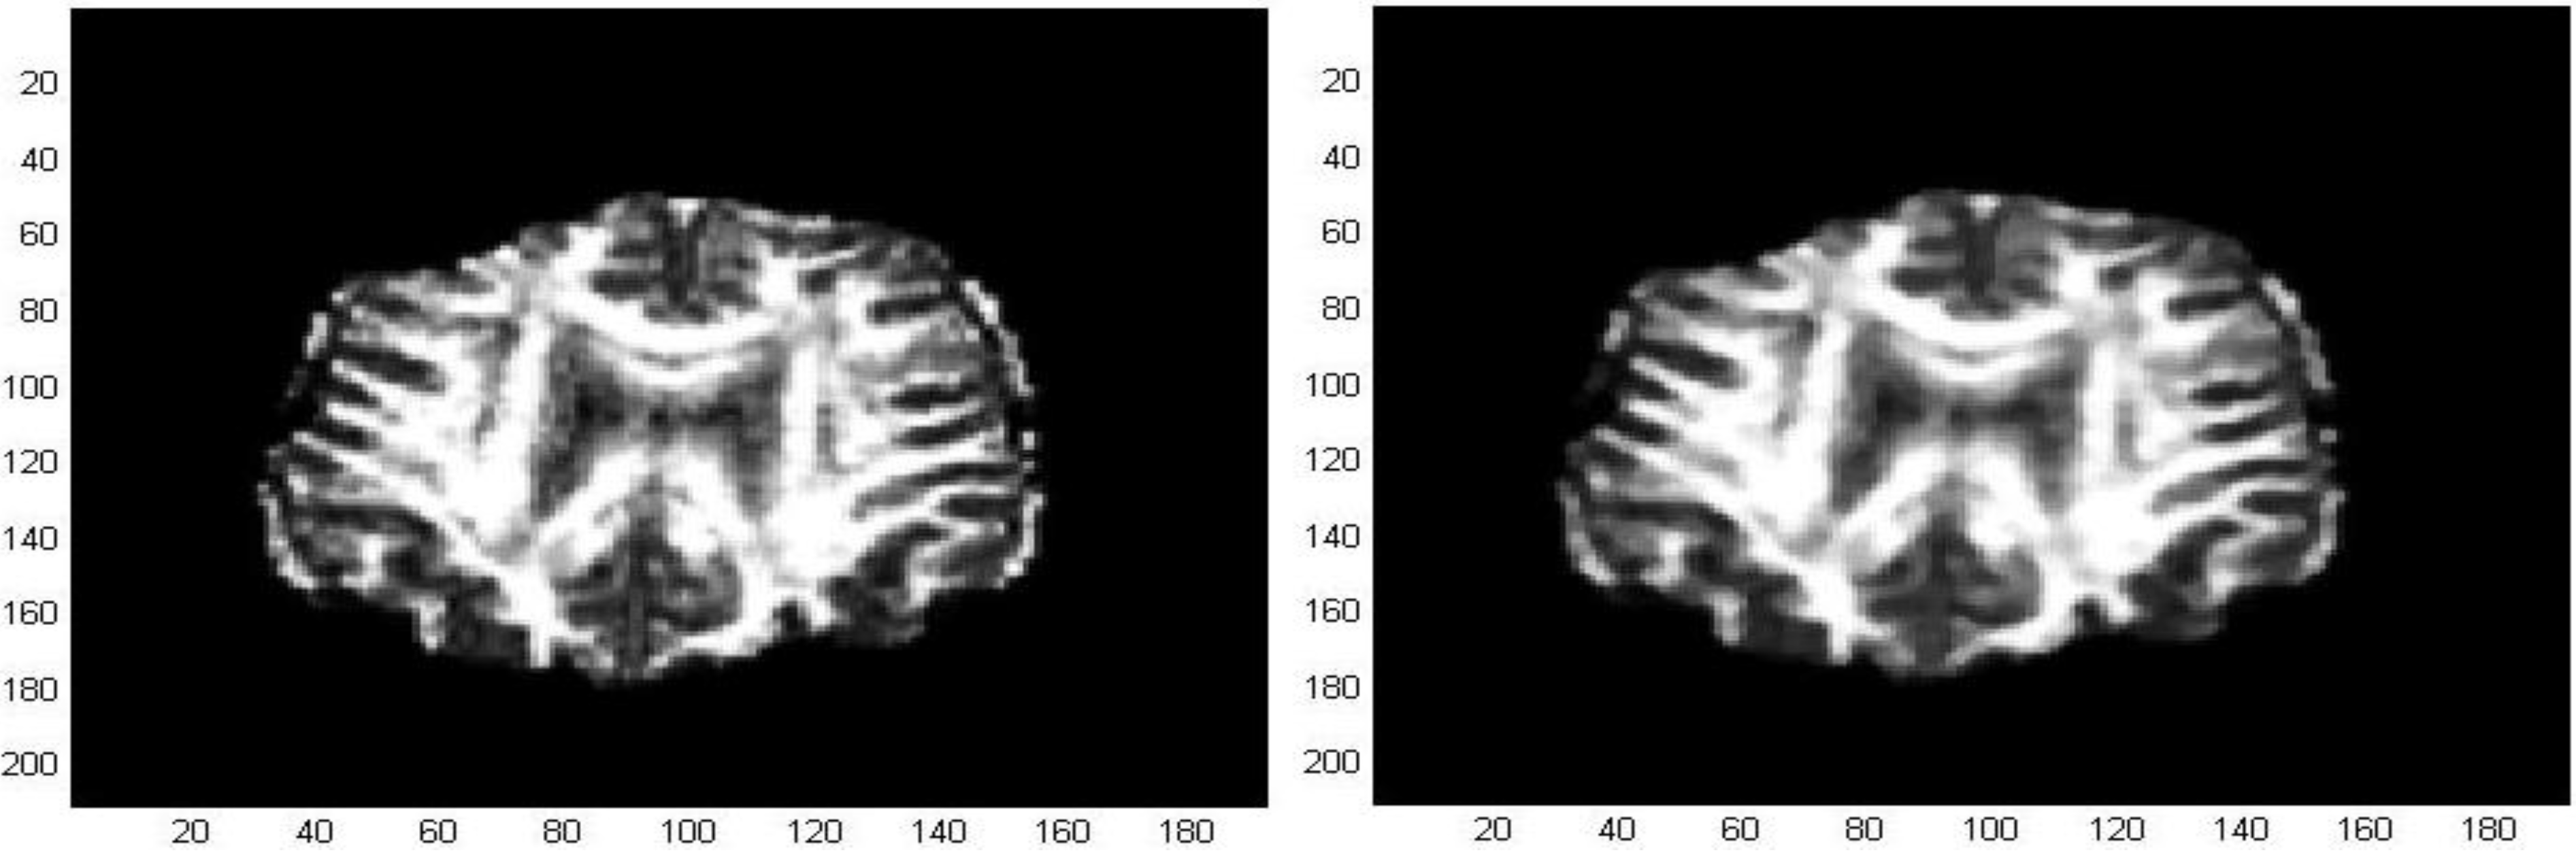

The processed GM and FA images were derived from a dataset composed by a group of 17 patients affected by Alzheimer’s disease and a control group of 11 unities. MRI images were acquired using a 3 Tesla Siemens Impact scanner at the Neuroradiology Unit of the Ospedale Maggiore Borgo Trento, Verona, Italy (2008) with a standard head coil. Axial diffusion tensor images (DTI) were acquired with diffusion encoding gradients applied in thirty noncollinear directions and a b-factor of 1000 s/mm2, plus five images without diffusion weighting. The following parameters were used: TR = 5000 ms, TE = 118 ms, number of slices = 23, slice thickness = 5 mm, slice gap = 1 mm, acquisition matrix = 128 × 128, FOV = 220 mm, the scan duration was 3 min. FA and directional maps for two subjects are shown in Figure 9, the images were realized by using the Software Tools FSL 4.0 (Figure 9 and Figure 10) (Functional Software Library of the FMRIB Centre, Oxford Centre for Functional Magnetic Resonance Imaging of the Brain-Oxford University) [18,19].

Figure 9. FA and directional Maps derived by the Software Tools FSL.

Figure 10. Segmentation of a gray matter image (GM), derived by the Software Tools FSL.